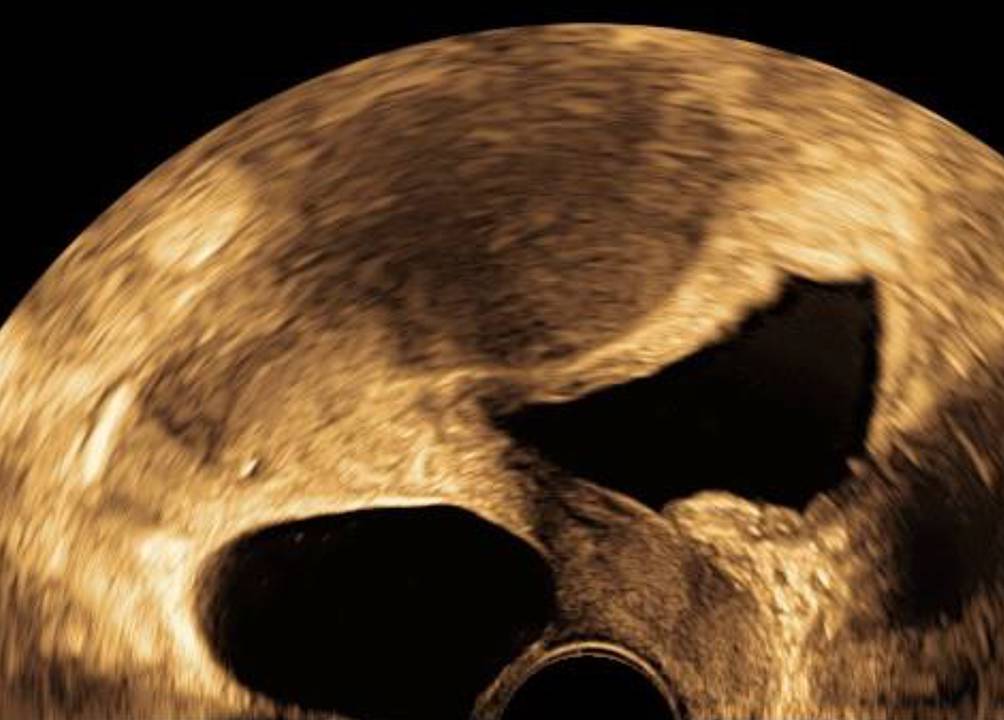

Abb. 5

3‑D-Aufnahme eines transurethralen Verweilkatheters in einer fast leeren Harnblase im Vaginalschall. Der mit Blockiermedium gefüllte Ballon wird durch den Katheter durchquert